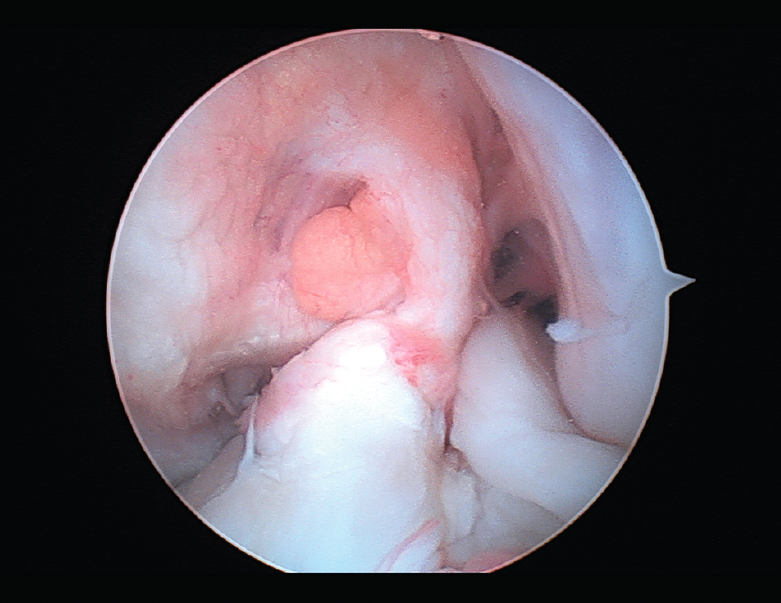

El tratamiento de un paciente que sufre una rotura aguda del LCA (Figura 2) sigue siendo motivo de discusión(9). Hay muchos condicionantes que influyen en el manejo terapéutico de estas lesiones (ya sea quirúrgico como no quirúrgico), como son la edad, la ocupación, la actividad deportiva, las lesiones asociadas, el grado de laxitud de la rodilla, las expectativas o las recidivas de la lesión, entre otras. El riesgo de artrosis tras la rotura aguda del LCA será mayor en ambos grupos con respecto a la población sana, sea cual sea el tratamiento(12). Los factores de riesgo más importantes para el desarrollo de artropatía son: lesión meniscal, meniscectomía e injerto hueso-tendón-hueso (HTH).

Figura 2. Rotura aguda del ligamento cruzado anterior.